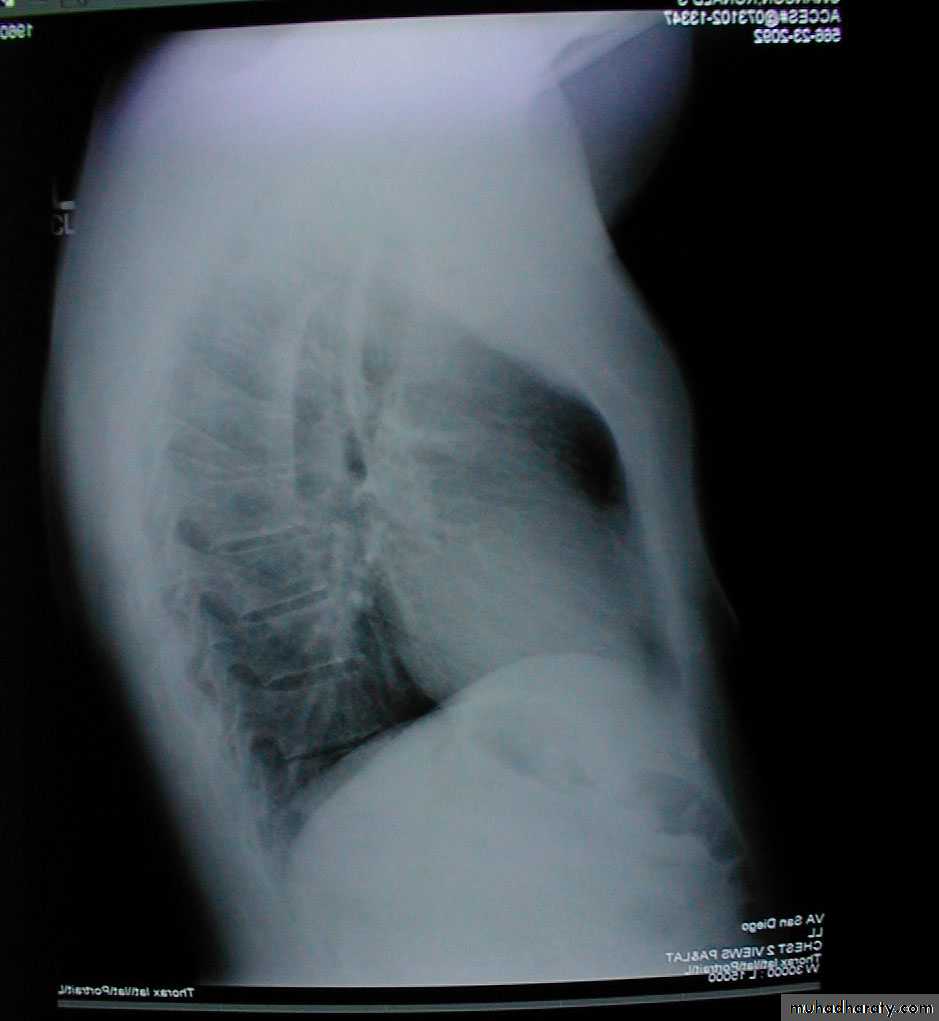

Pectus excavatum: Congenital posterior displacement of lower aspect of sternum. This gives the chest a somewhat "hollowed-out" appearance. The x-ray shows a subtle concave appearance of the lower sternum.

Pectus excavatum

Barrel chest: Associated with emphysema and lung hyperinflation. Accompanying xray also demonstrates increased anterior-posterior diameter as well as diaphragmatic flattening.